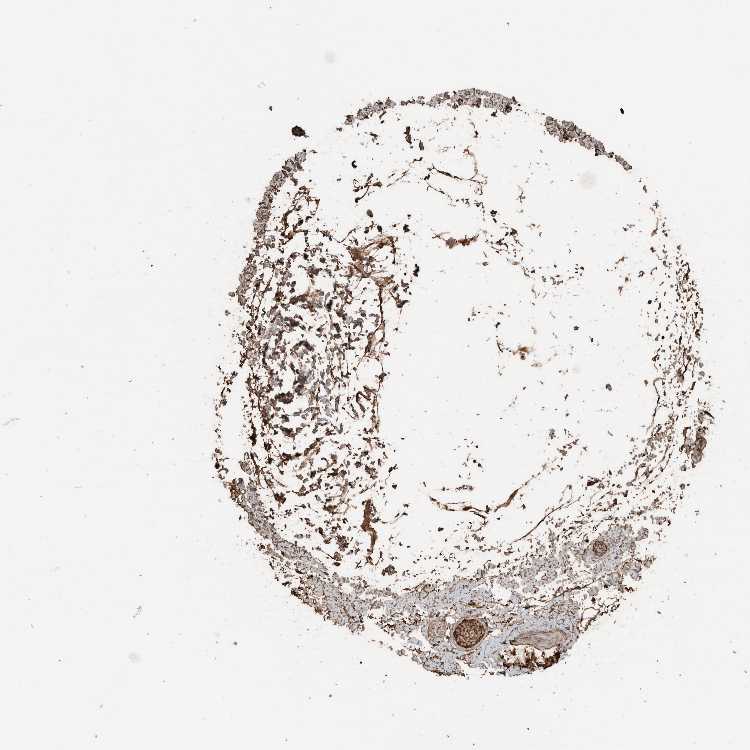

ADIPOSE TISSUE - Antibody stainingi

Antibody staining in the annotated cell types in the current human tissue is reported as not detected, low, medium, or high, based on conventional immunohistochemistry profiling in selected tissues. This score is based on the combination of the staining intensity and fraction of stained cells.

Each image is clickable and will lead to virtual microscopy that enables deeper exploration of all samples and also displays staining intensity scores, fraction scores and subcellular localization as well as patient and tissue information for each sample.

Antibody HPA025815

Adipocytes Medium